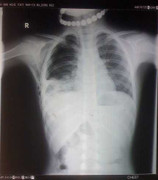

(VTC News) – Đang chơi cùng bạn, bất ngờ con trâu lao thẳng vào người khiến cháu T chấn thương rất nặng, người lơ mơ, khó thở, gãy xương sườn…

(VTC News) – Bị trâu húc trong khi cùng bạn đi ngang qua cánh đồng, cháu X bị chấn thương nặng vùng ngực, người xây xát, khó thở, tràn máu, tràn khí màng phổi.